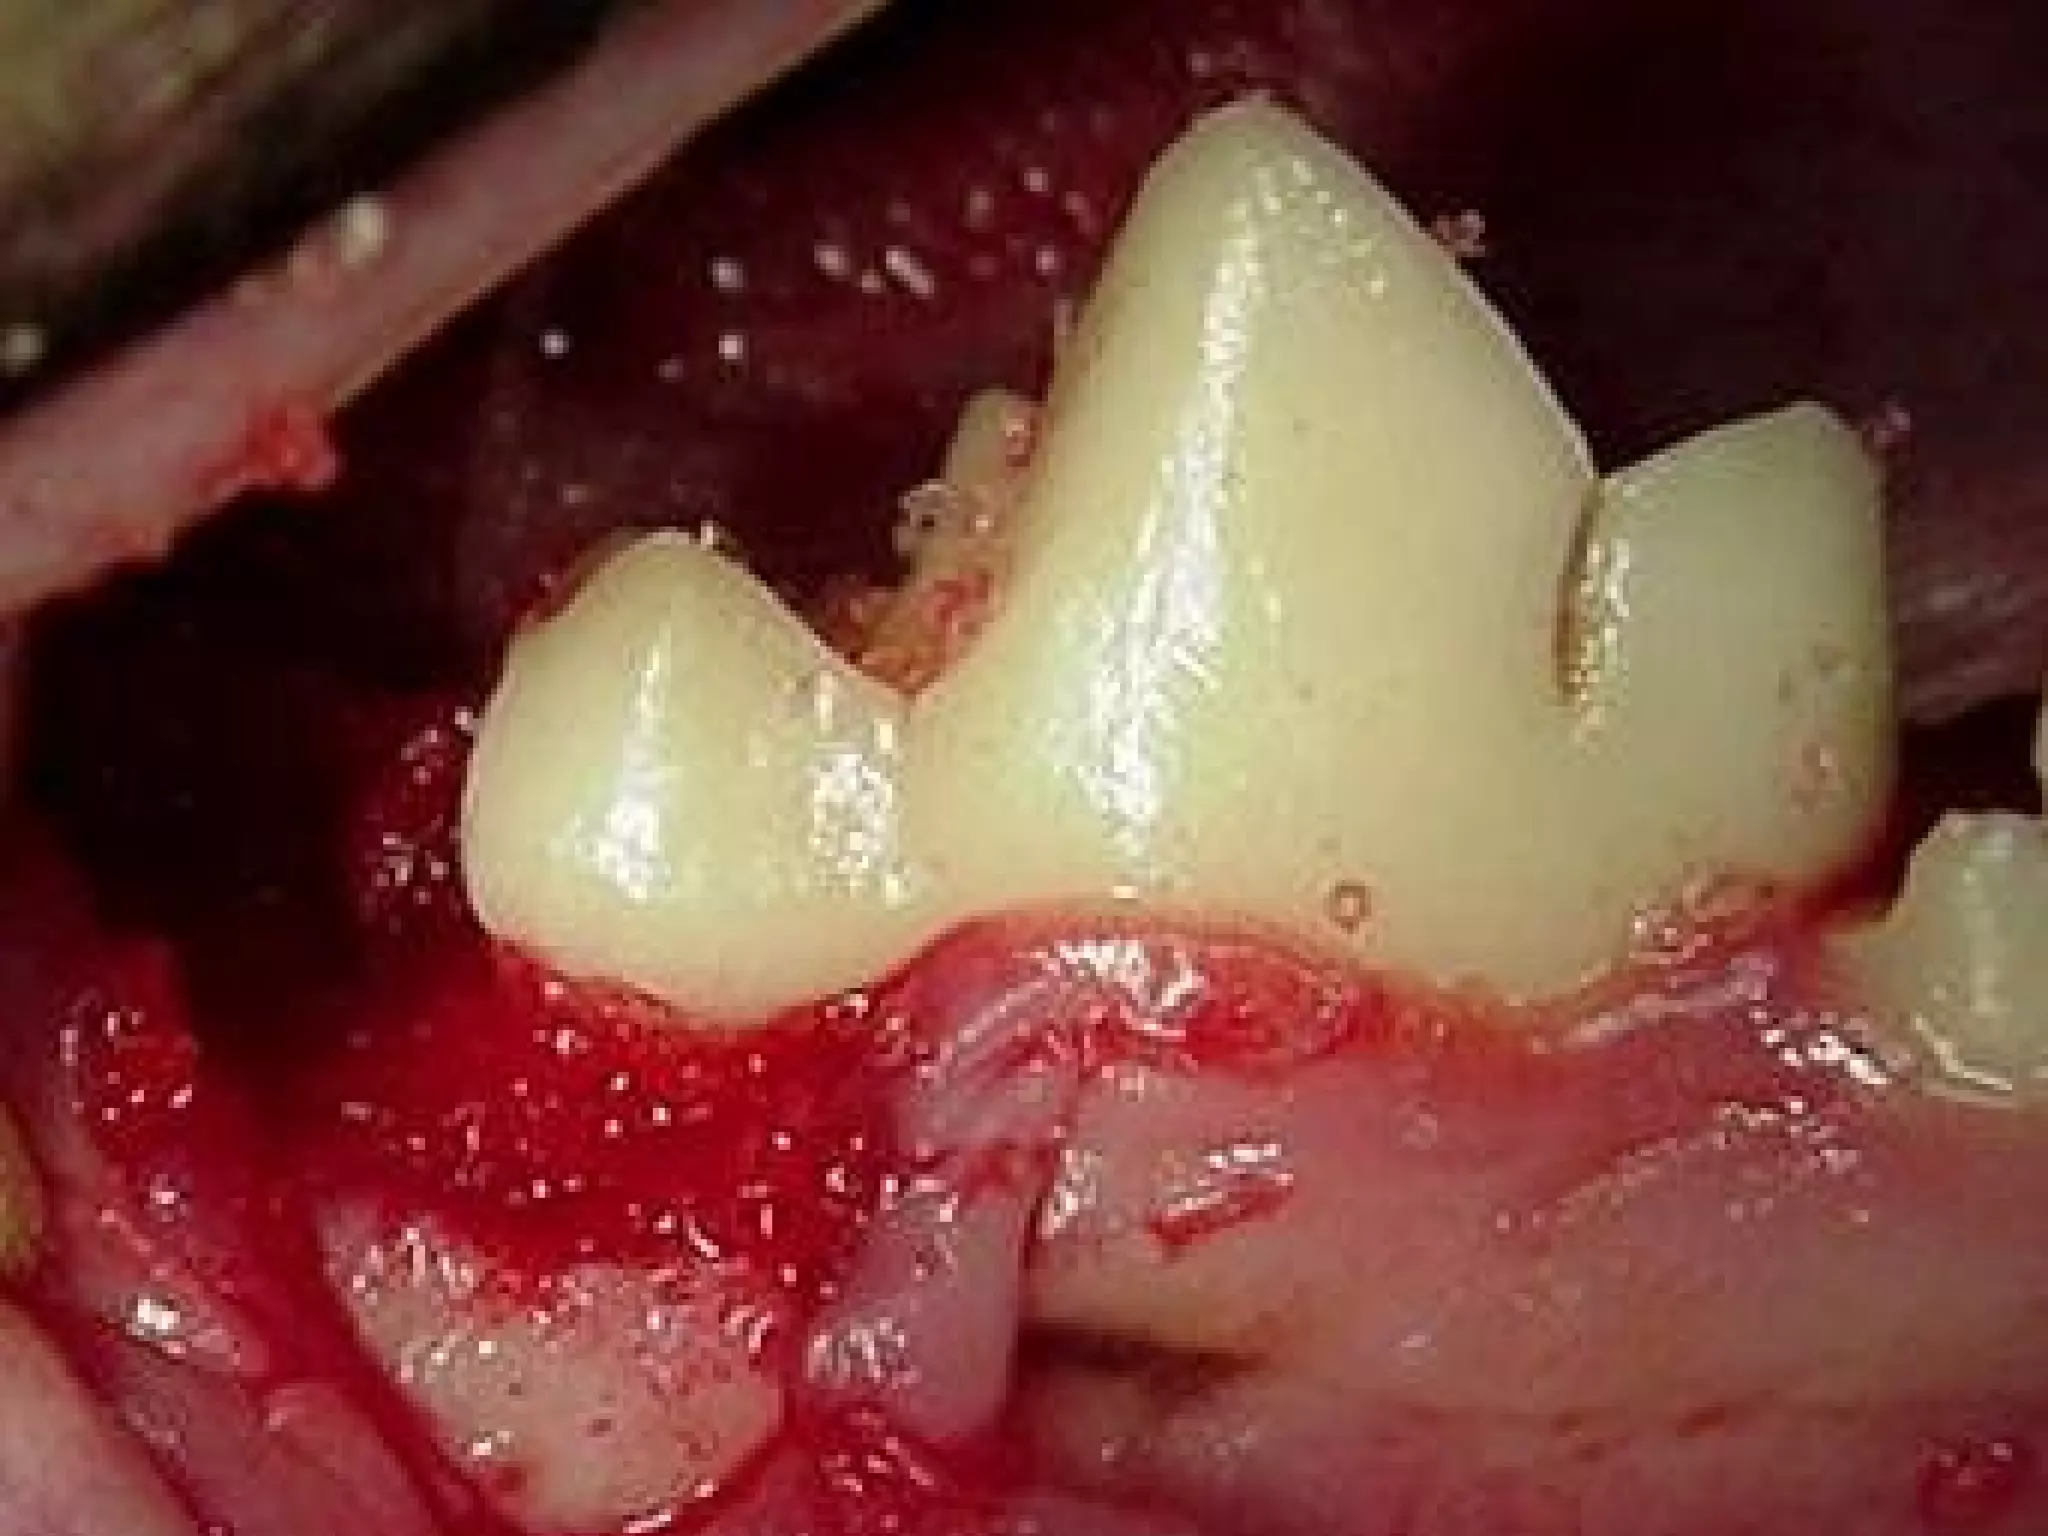

What is the disease present here?

Anatomical description of the

affected tooth?

• 38.

What is thedisease present here? Anatomical description of the affected tooth? 38